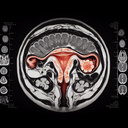

МРТ малого тазу у жінок

Магнітно-резонансна томографія (МРТ) малого тазу у жінок – це неінвазивний метод діагностики, який використовує магнітні поля та радіохвилі для отримання детальних зображень органів і тканин цієї області. **Основні переваги:** 1. **Висока точність:** Допомагає виявити захворювання на ранніх стадіях...